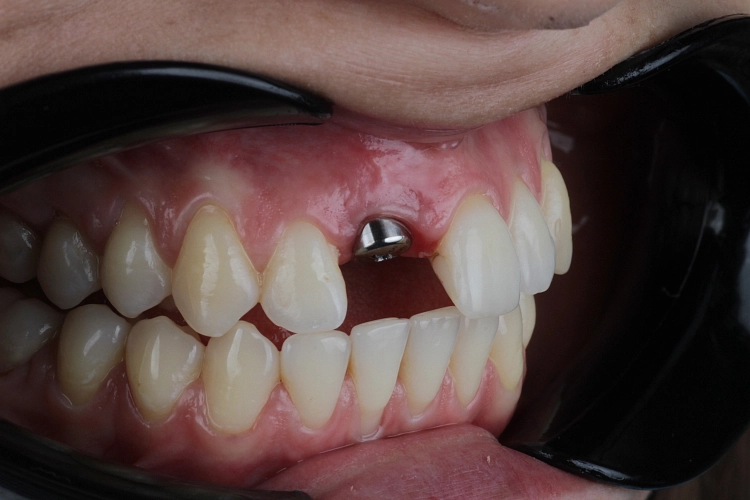

Одномоментно – имплант устанавливают сразу после удаления разрушенного корня в одно посещение;

Рекомендуемый срок установки импланта после потери зуба - 3-6 месяцев. Больший период выжидать мы не советуем, если пройдет больше времени, то могут возникнуть проблемы: атрофия костной ткани, и для того чтобы установить имплант понадобятся дополнительные процедуры (наращивание костной ткани и т.д.)